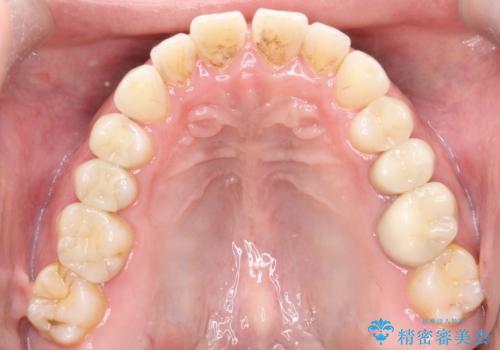

【インビザライン】前歯の隙間を閉じたい

- 前歯の隙間を主訴に来院されました。

マウスピース矯正にて、隙間を綺麗に閉じることができ満足していただきました。

前歯の隙間を閉じる際は、前歯部の突き上げが懸念されるため、適切な治療計画が必要となります。